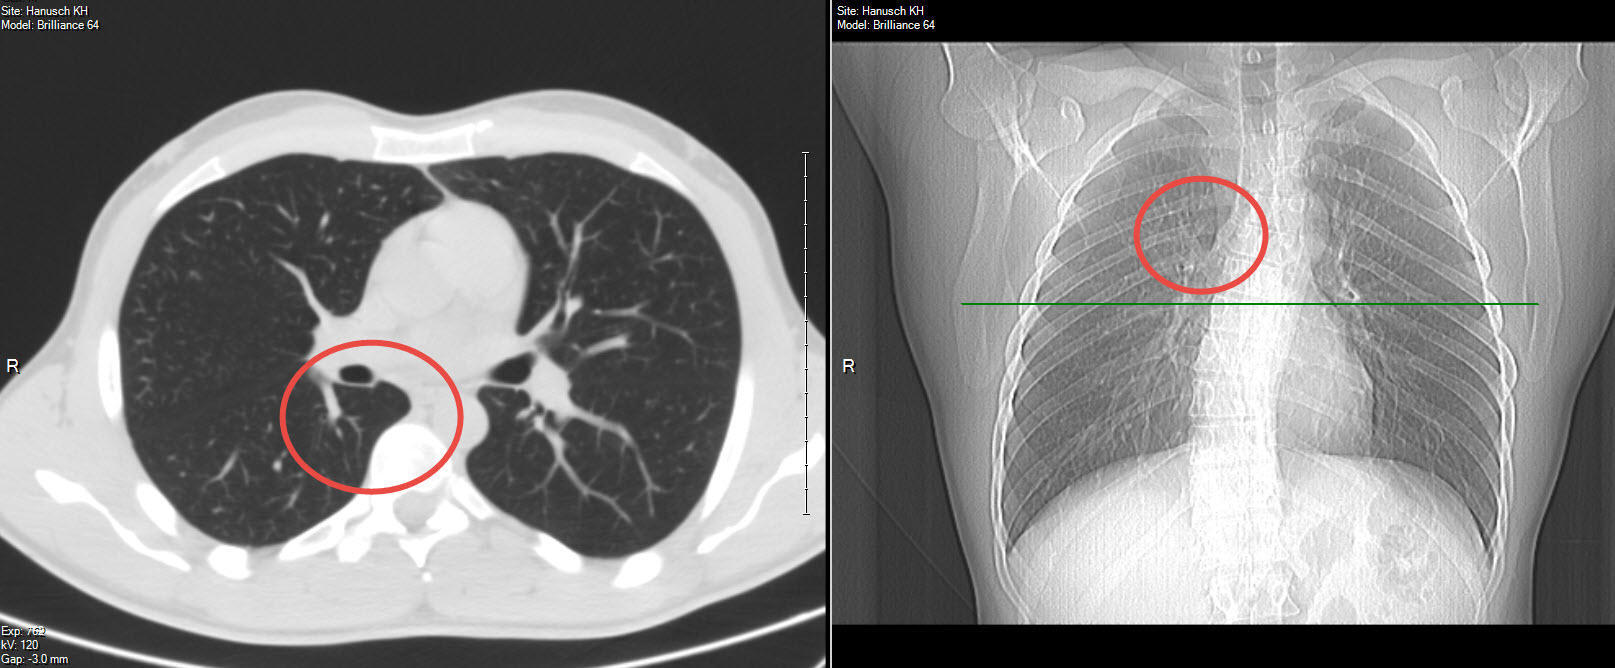

In der frontalen Ansicht der rote Kreis entspricht meiner Meinung nach der Punkt woher die Schmerzen kommen.

Im Schnitt in rot eingekreist, ist die Stelle wo ich vermute, dass es zur einer Quetschung der Lunge beim tiefen Einatmen kommt.

Der grüne Strich in der frontalen Aufnahme entspricht der Höhe des Schnittbildes.

Anbei das Bild: